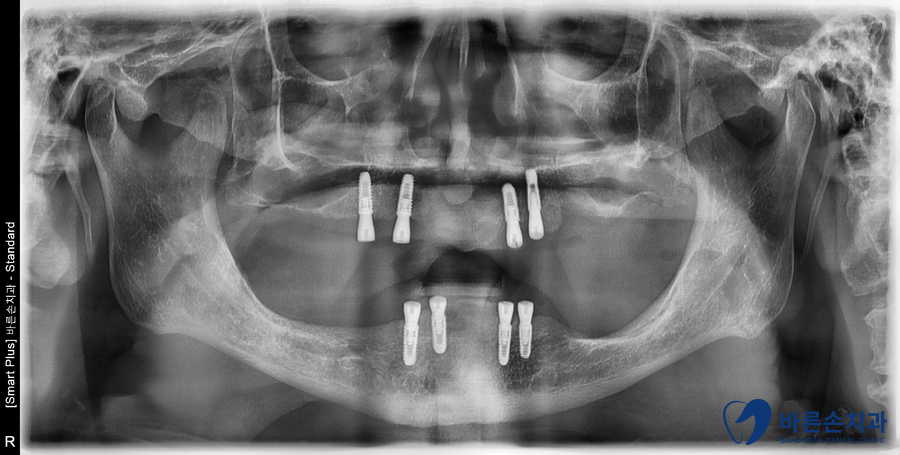

치아를 모두 발치 후,

뼈이식과 동시에 상악에 4개, 하악에 4개 임플란트를 식립하였습니다.

3개월 후,

임플란트와 치조골이 얼마나 단단하게 결합되었는지

임플란트 안정성 수치=ISQ(Implant stability Quotient)를 측정해보고

임플란트가 뼈랑 결합이 잘 된것을 확인 후 틀니를 걸어 쓸 치아를 만듭니다.

앞니 임플란트 보철물이 나왔고 세팅을 합니다.

상악은 임플란트 픽스쳐 4개로 8개의 치아를,

하악은 임플란트 픽스쳐 4개로 7개의 치아를 만들었습니다.

상, 하악 모두 브릿지 형태이며

그 위에 틀니가 걸릴수 있게 Surveyed 크라운으로 제작하였습니다.